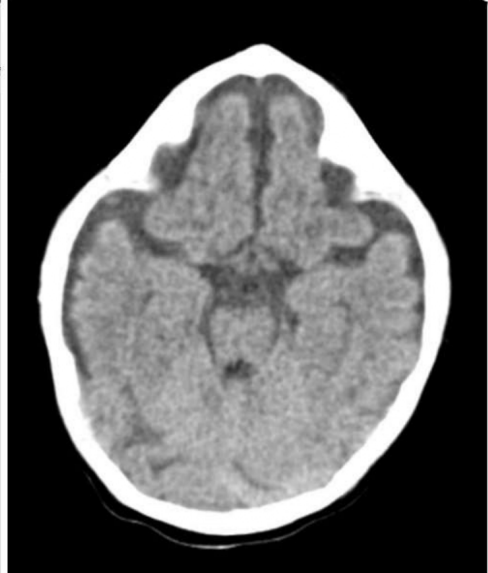

A 12-year-old African-American male with a history of asthma presents with fever, lethargy, seizure activity, and left hemiparesis.

Inflammatory markers are elevated. After stabilization, a CT head with contrast is obtained (figure). What is the most appropriate next

step in management?

Craniotomy